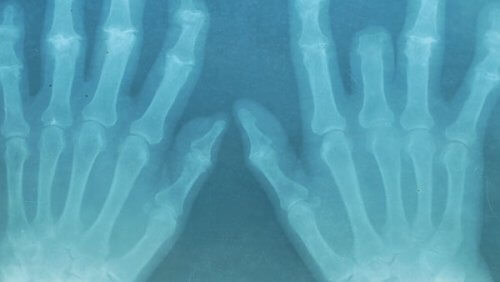

Bewegingsproblemen worden steeds gebruikelijker. Helaas zijn er geen efficiënte langetermijnbehandelingen voor deze aandoeningen. Daarom raden we je aan om gebruik te maken van etherische olie om spier- en gewrichtspijn te verminderen.

Deze aandoeningen worden veroorzaakt door veel dingen, van blessures na het sporten of het hebben van een slechte houding tot aan natuurlijke afbraak veroorzaakt door het ouder worden.